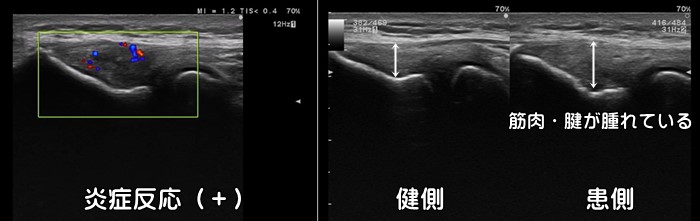

外側上顆炎・テニス肘

肘の外側に痛みがあれば外側上顆炎(テニス肘)が疑われます。テニス選手に多い障害ですが、重いお鍋やフライパンを持つ主婦の方にも発症します。エコーでは短橈側手根伸筋の付着部の低エコー像と肥厚、外側上顆部の骨棘が見られます。炎症反応の動画はこちらで確認できます。